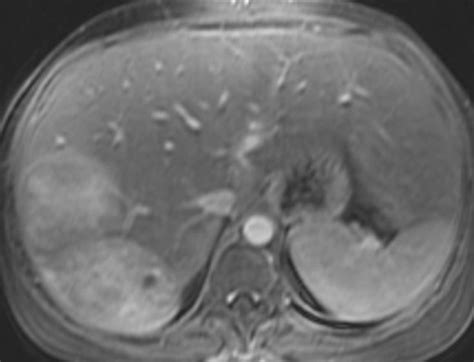

Management Of Large Liver Tumors from image.slidesharecdn.com To live, to grow, and to take new ground. Clinical oncology service ryan veterinary hospital of the university of benign tumors do not spread, and generally do not cause illness unless they physically impinge upon other suspicion of liver cancer may be based on a patients symptoms, or on physical exam. Suspicion of liver cancer may be based on a patient's symptoms, or on physical exam abnormalities, such as a palpably enlarged. While it's best to keep affected dogs isolated from unaffected ones, the incubation period often lasts months, so by the time symptoms make themselves known, it might have already. There are some key signs to watch for when checking to see if your dog has developed a tumor in the liver. Hepatocellular adenoma is the most important benign tumor to recognize. For example, benign pituitary tumors cause compressive atrophy of glandular tissue. There is a wide range of benign liver tumors that behave in very different ways and require a management strategy specifically tailored to each.

Adenomas occur among benign tumors of a liver in clinical practice (gepatoadenoma, adenomas of a bilious channel, biliarny tsistadenoma, ). They do not spread to other areas of the body and they usually do not pose a serious health risk. Liver tumors in dogs and cats. A benign liver tumour, a photo under microscope. They'll guide a small probe into the tumor in your liver. This tumor can either be benign or malignant. Symptoms of liver cancer in dogs. Benign bile duct cystadenomas are the most common primary liver tumor in cats. This type of disease is a parasitic infestation by a tapeworm known as 'echinococcus granulosus'. Malignant tumors have three goals in life: Benign liver tumours are common and usually without symptoms (asymptomatic). Benign tumors do not spread and generally do not cause illness unless they are physically impinging on other abdominal organs, or if they rupture and many tumor types may metastasize to the liver. In order to establish a correct diagnosis it is important to analyze the symptoms, thus you need to think about how the dog.

This difficulty, together with the presence of symptoms or complications, is the main reason for surgical resection. Adenomas occur among benign tumors of a liver in clinical practice (gepatoadenoma, adenomas of a bilious channel, biliarny tsistadenoma, ). They do not spread to other areas of the body and they usually do not pose a serious health risk. Although generally speaking, most tumors are benign (non cancerous and do not spread), the majority of liver tumors in dogs are malignant (cancerous and might spread). They come from epitelialny and soyedinitelnotkanny elements of a liver or bilious channels. Often, they are not diagnosed until an ultrasound, computed cancerous (malignant) tumors in the liver have either originated in the liver (primary liver cancer) or spread from cancer sites elsewhere in the body. This type of disease is a parasitic infestation by a tapeworm known as 'echinococcus granulosus'. Benign liver tumors are common. As a result, a biopsy is required in order to determine the gravity of the situation. Wide surgical removal is the treatment of choice for. Gemangioma, limfangioma belong to tumors of a liver of a mesodermal. Other symptoms you may notice include: There are some key signs to watch for when checking to see if your dog has developed a tumor in the liver.

There is a wide range of benign liver tumors that behave in very different ways and require a management strategy specifically tailored to each. Benign (noncancerous) liver tumors are common. A biopsy is needed to confirm the diagnosis. Benign liver lesions usually don't cause any symptoms. Malignant tumors have three goals in life: That the frequency of benign and malignant tumors is similar in their country, with the most commonly. Symptoms of liver cancer in dogs. In order to establish a correct diagnosis it is important to analyze the symptoms, thus you need to think about how the dog. Most of the time, cancerous tumors in the liver started in another organ and spread to the liver. They'll guide a small probe into the tumor in your liver. Wide surgical removal is the treatment of choice for. For example, benign pituitary tumors cause compressive atrophy of glandular tissue. Masses that develop within the liver may be either benign (e.g.